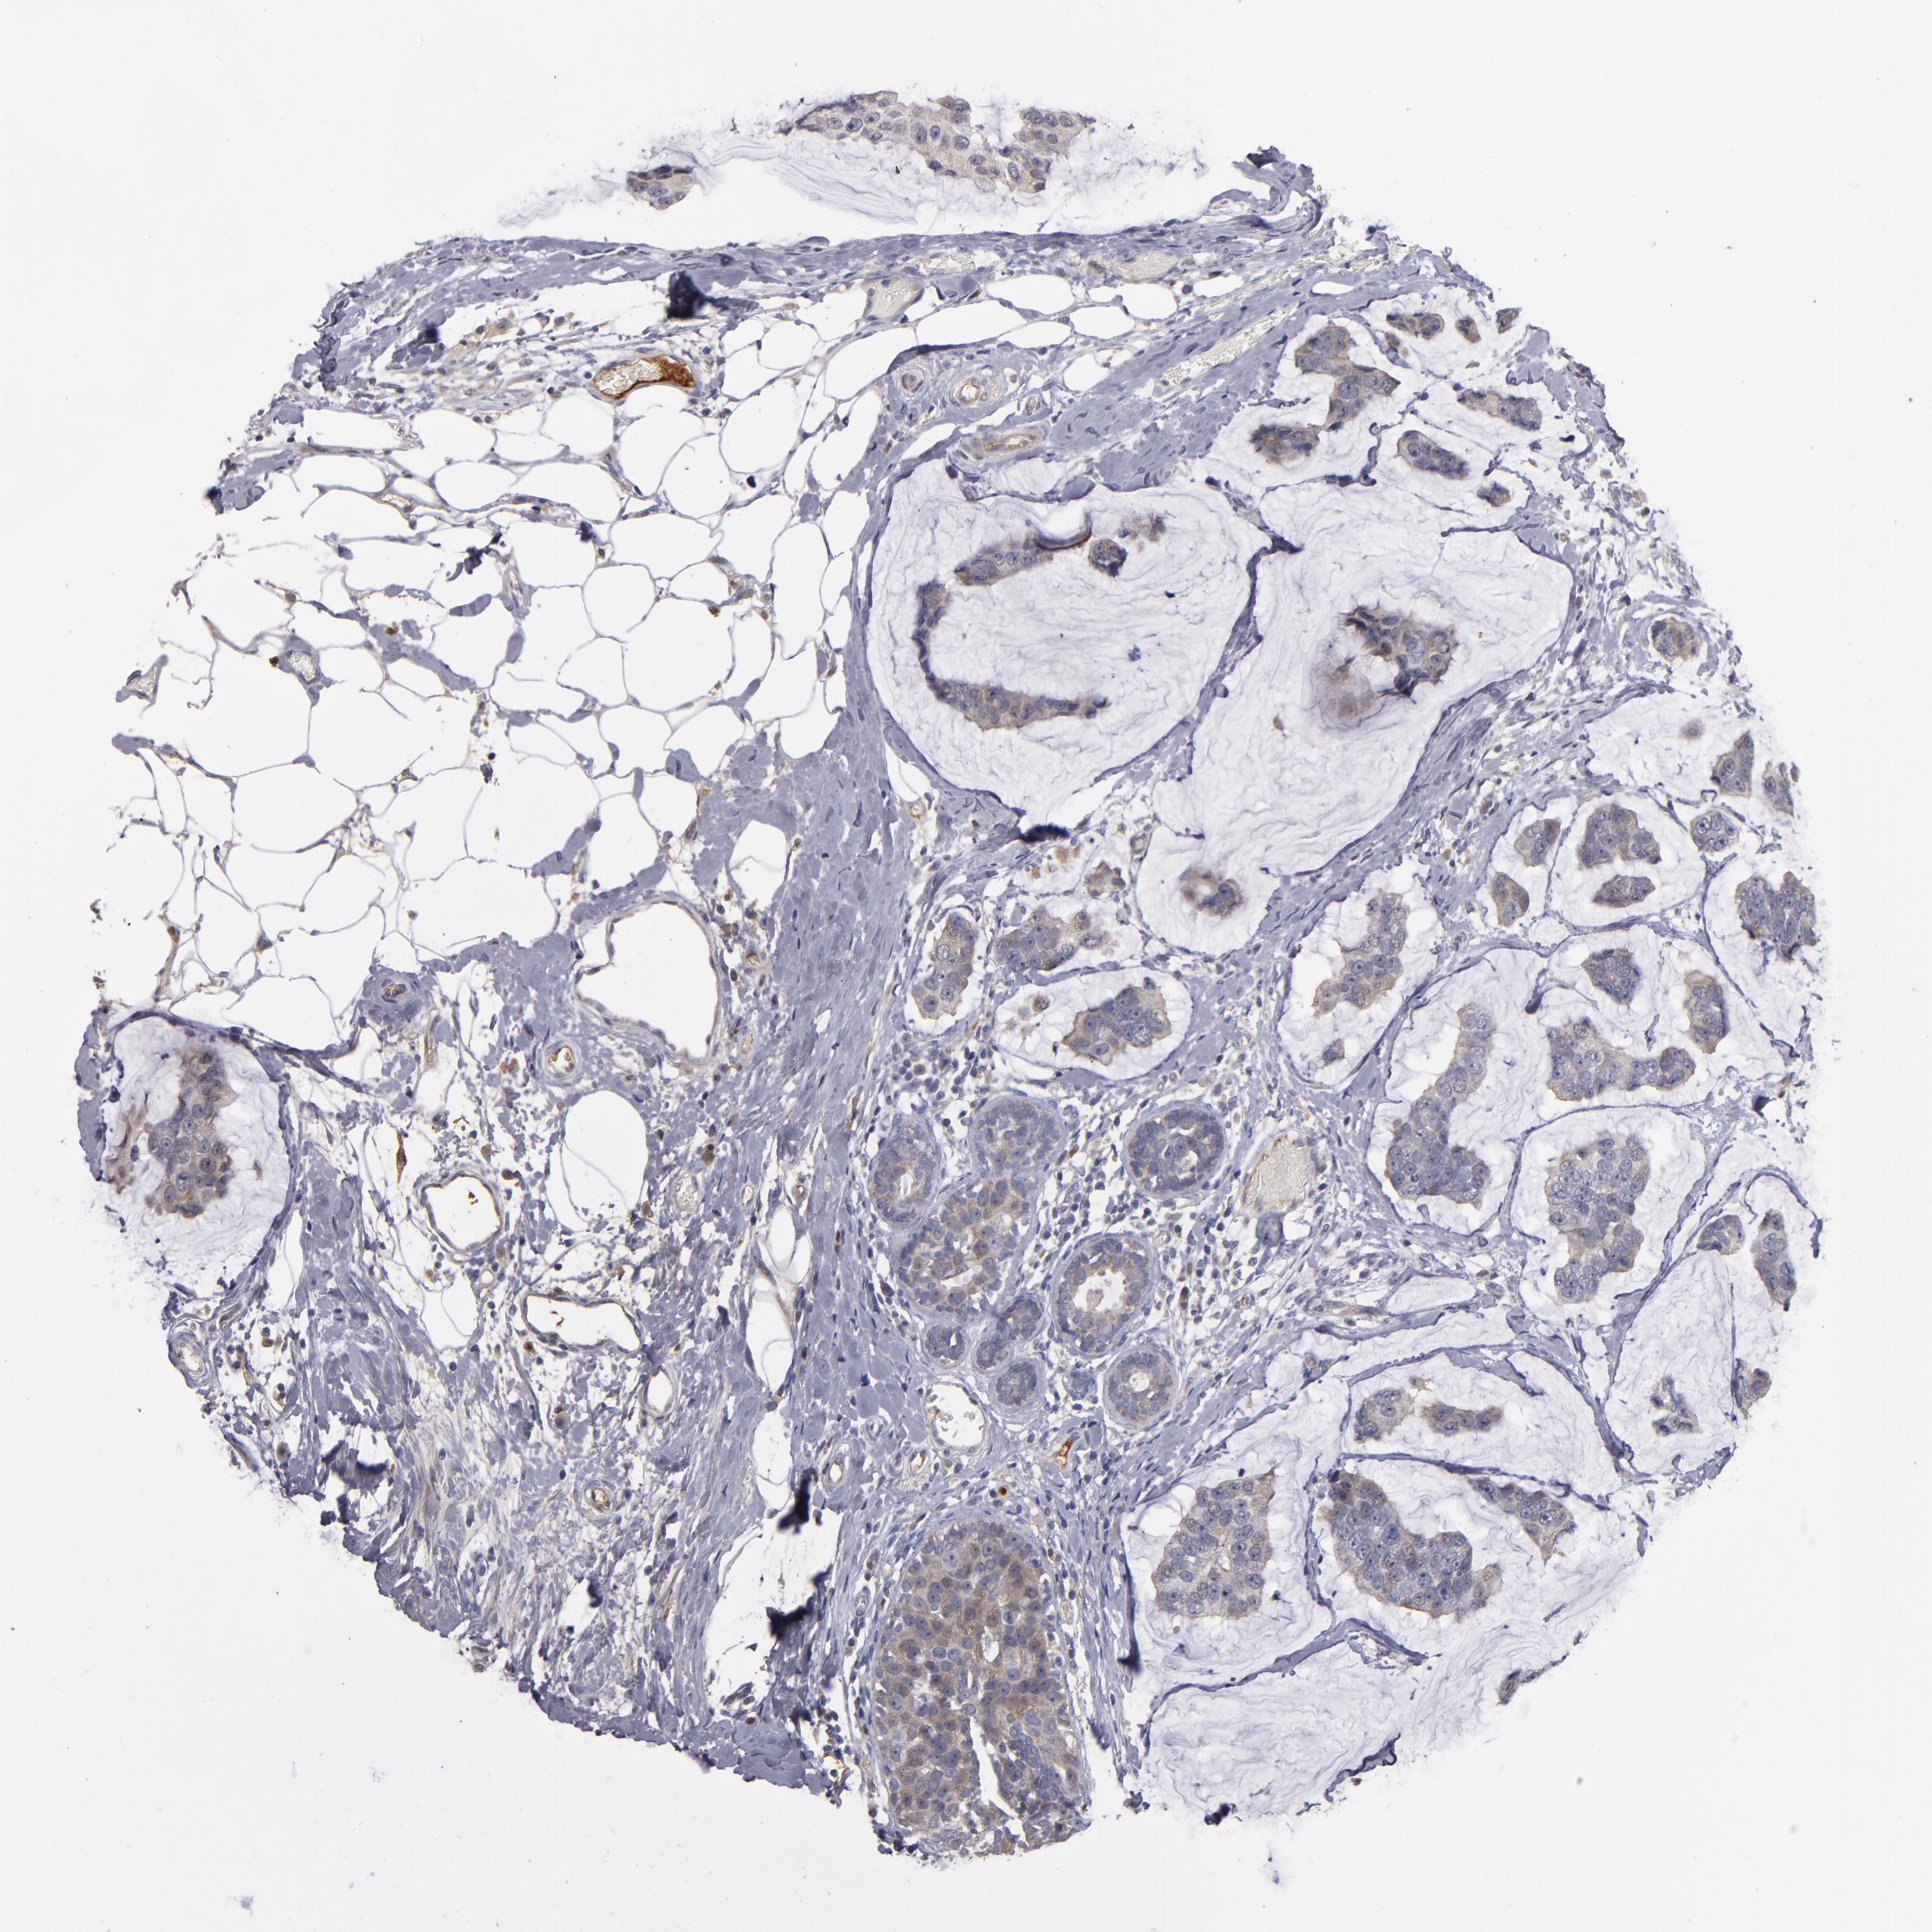

CANCER BREAST CANCER Show tissue menu

BRCA TCGA BRCA VALIDATION PROTEIN EXPRESSION

Breast cancer

Human cancer

Breast invasive carcinoma